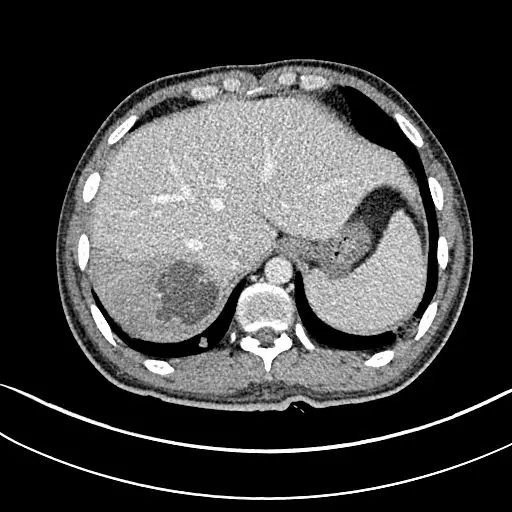

CT:双肺多发空洞、气囊、结节 , 病灶以胸膜下为主 , 见实变 , 胸腔积液 。 肝脓肿 。

肺炎克雷伯菌是引起肝脓肿的最常见病原体 , 以前的报道 , 肺炎克雷伯菌性 肝脓肿很少有肝外侵袭 , 但是 , 近些年发现 , 肺炎克雷伯杆菌 , 很容易导致 肝脓肿侵袭综合征:细菌全身多部位播散 ,肺、神经系统和眼是最常见的侵袭部位 。

送检脓液培养出:肺炎克雷伯菌 。 抗感染 , 肝脓肿穿刺引流 , 病情唰唰地好转 。